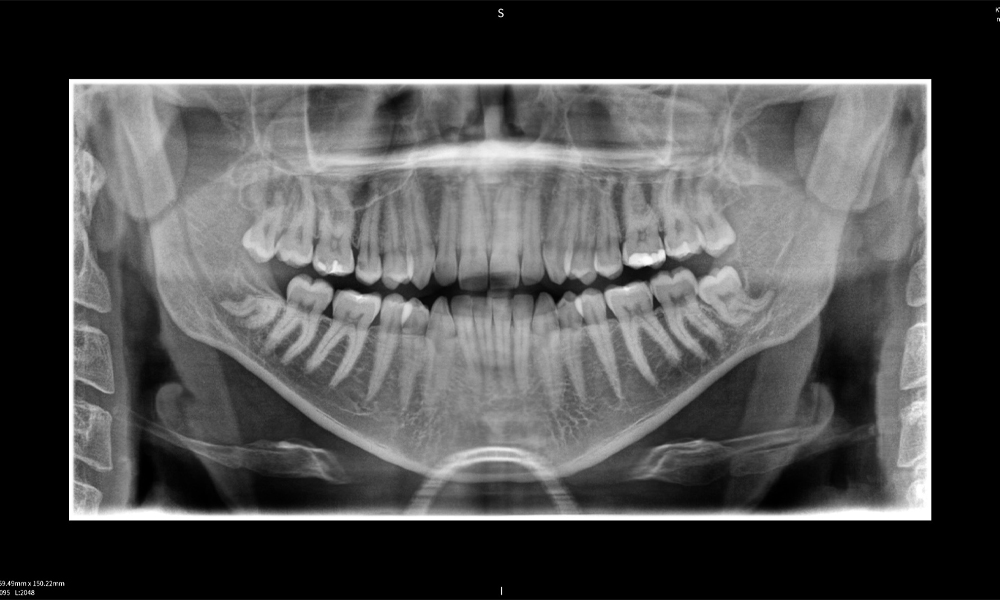

Figura e: Resultados de imagen de Seethrough Max, sobre un fondo negro.

Figura e: La radiografía panorámica sirve como herramienta de evaluación inicial, mostrando la posición general de los dientes, así como posibles cambios patológicos. Es notable que en el lado derecho (diente 48) se observa la situación posterior a una amputación de corona realizada por un profesional externo. Las dos raíces fuertemente curvadas permanecen en estrecha proximidad topográfica al nervio alveolar inferior dentro del hueso. Esto sugiere una decisión deliberada de evitar el mayor riesgo de lesión nerviosa durante una extracción completa y representa un hallazgo clínicamente relevante. En resumen, las tomografías CBCT con Seethrough Max proporcionan información crucial sobre la anatomía compleja y la relación crítica entre las muelas del juicio y el nervio alveolar inferior. Esta imagenología diagnóstica detallada preoperatoria es esencial para realizar procedimientos quirúrgicos seguros y exitosos en la región mandibular.